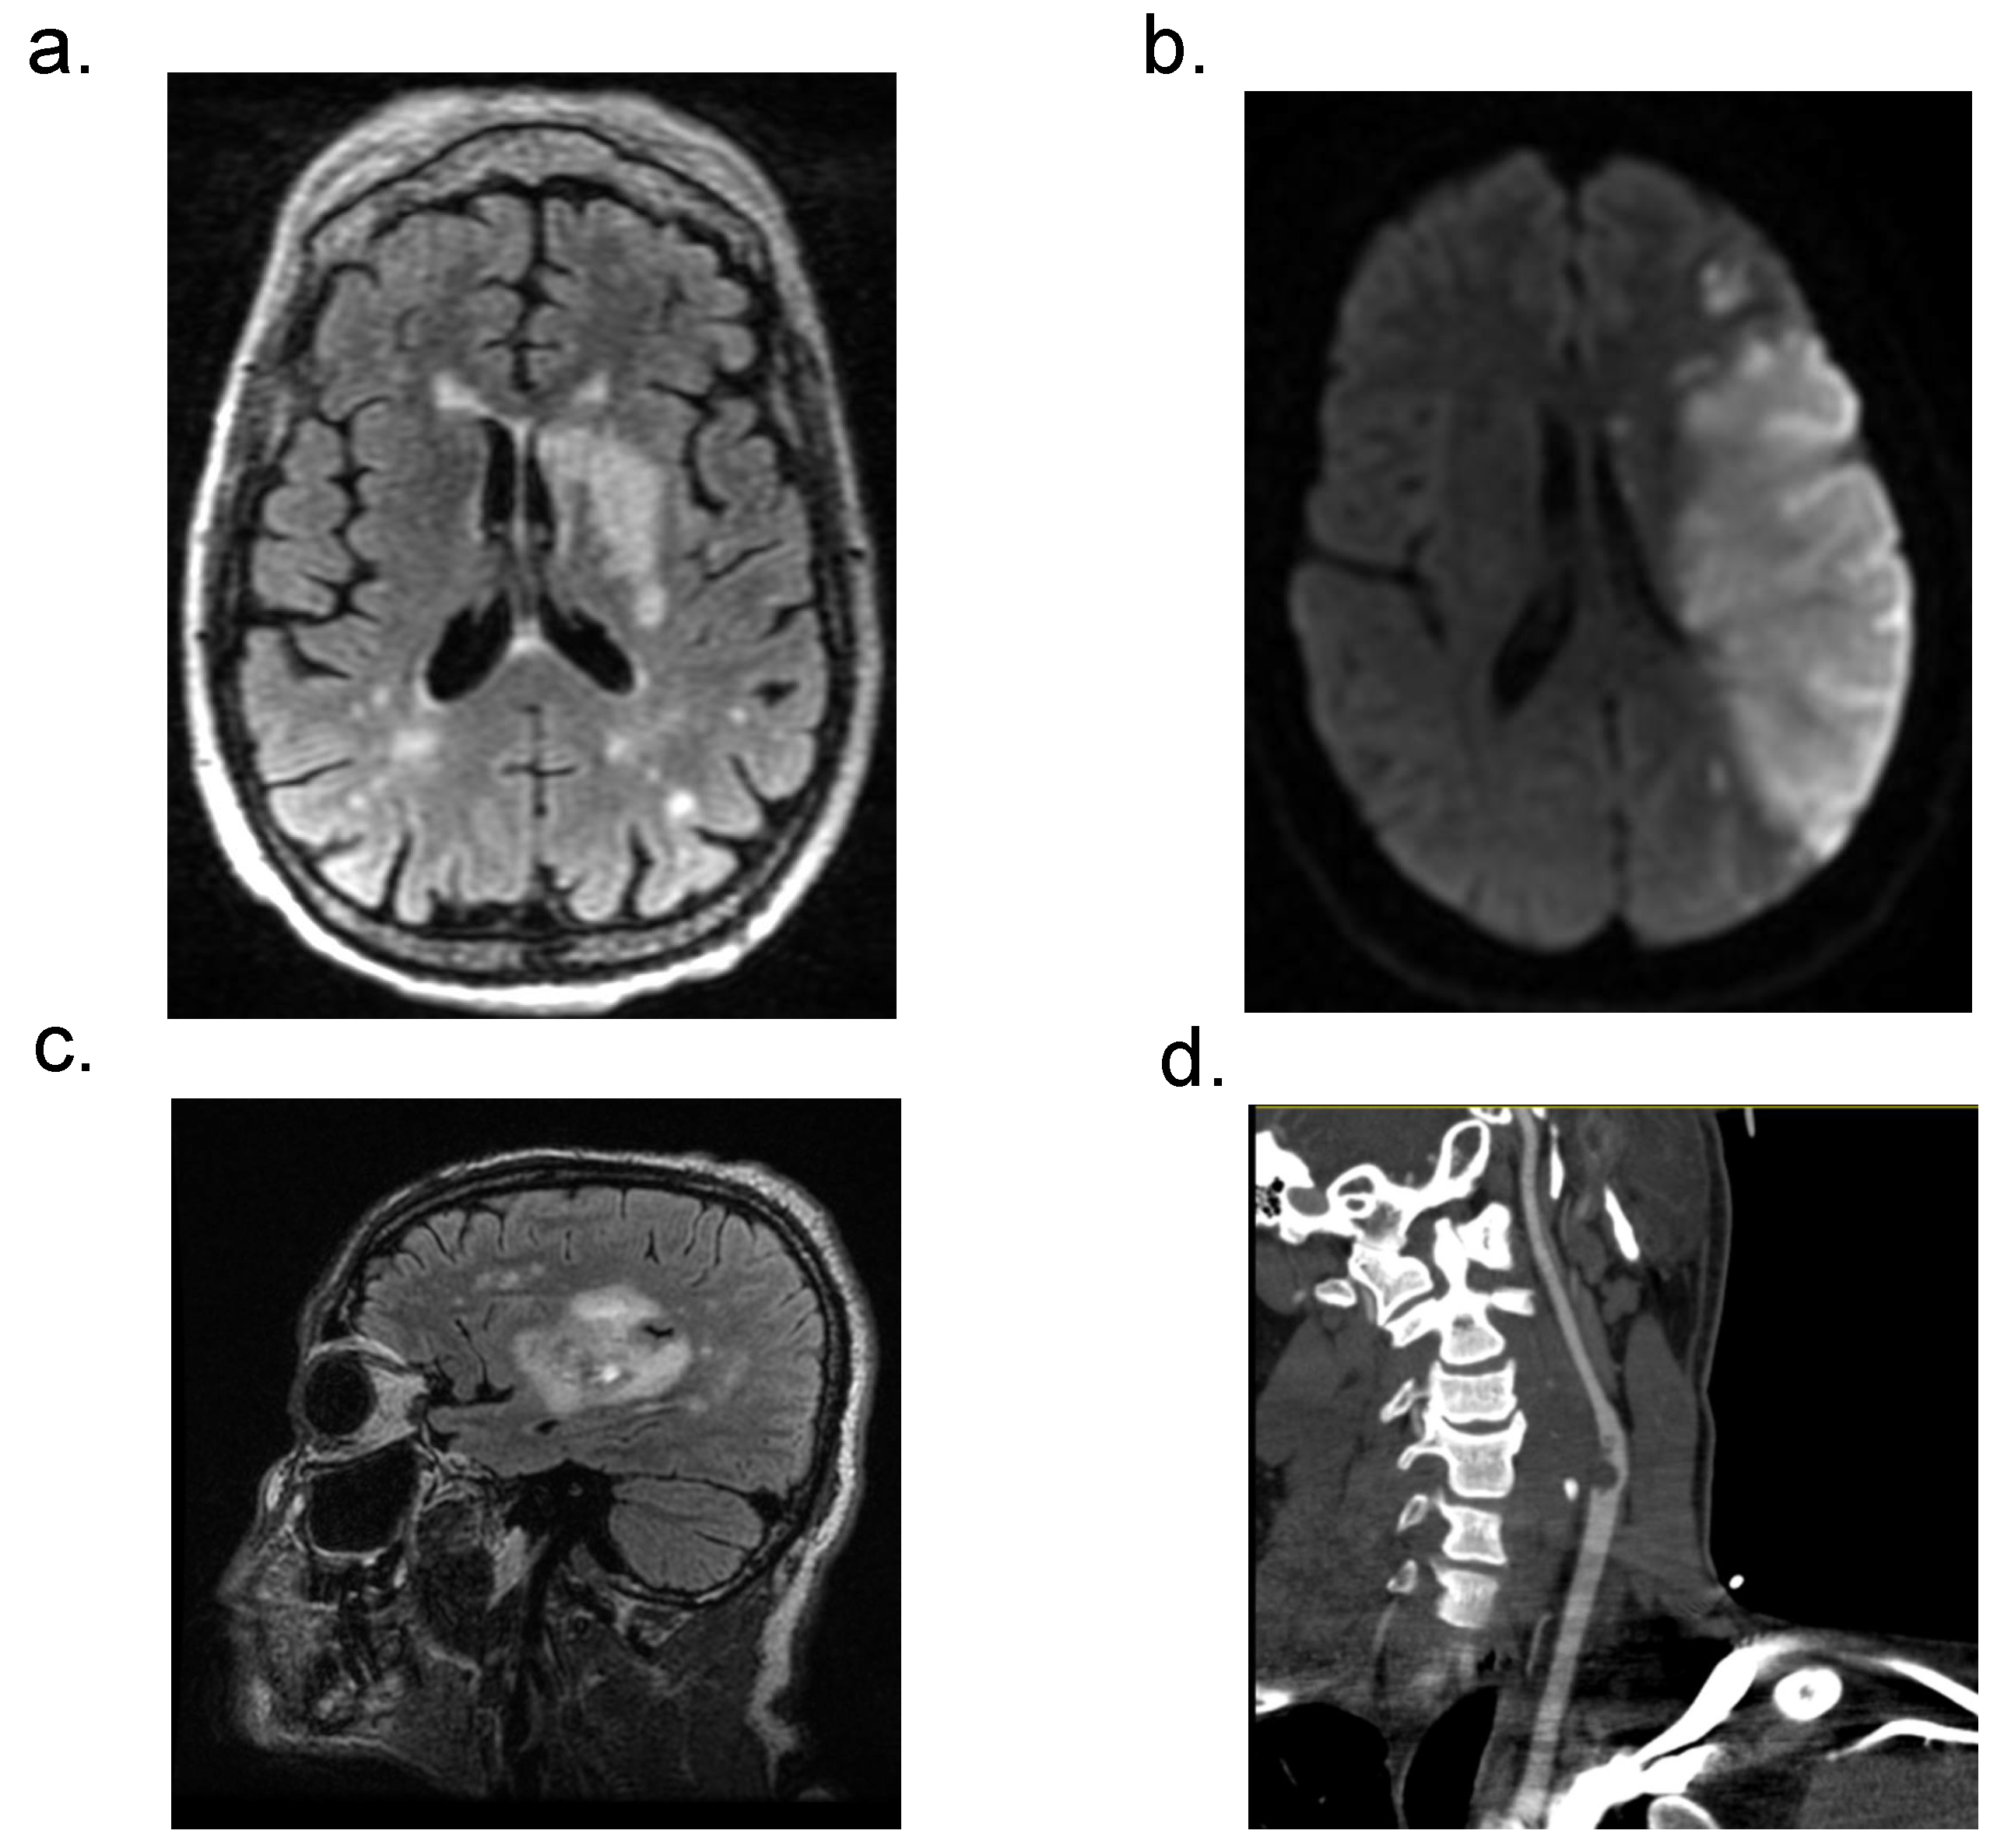

3.4. Neuroradiological Data of Patients with Acute CVD and COVID-19